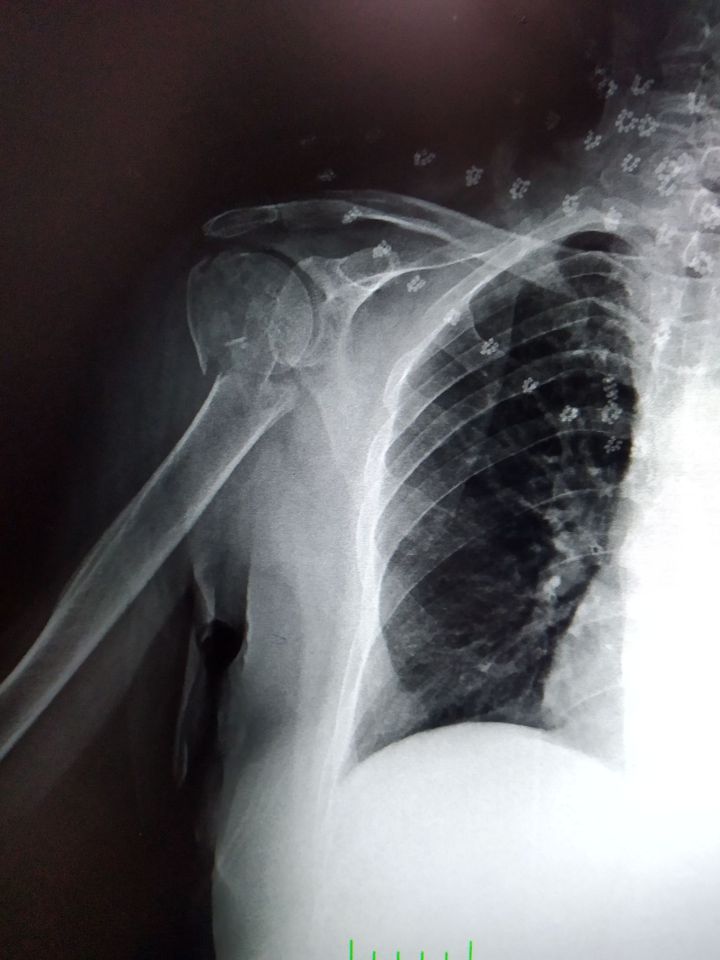

collum chirurgicum fraktur

67 years-old woman with a history of osteoporosis. She fell toward on her hand. Potential damage to axillary nerve and posterior circumflex humeral arter may occur due to fracture at surgical neck.